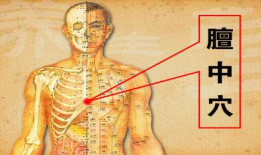

艾灸正确方法视频教程,掌握健康养生新技能

你有没有试过艾灸呢?那种暖暖的感觉,是不是让你瞬间觉得身体都轻松了呢?不过,你知道吗?艾灸虽然好,但如果没有正确的操作方法,效果...

2025-11-30 180